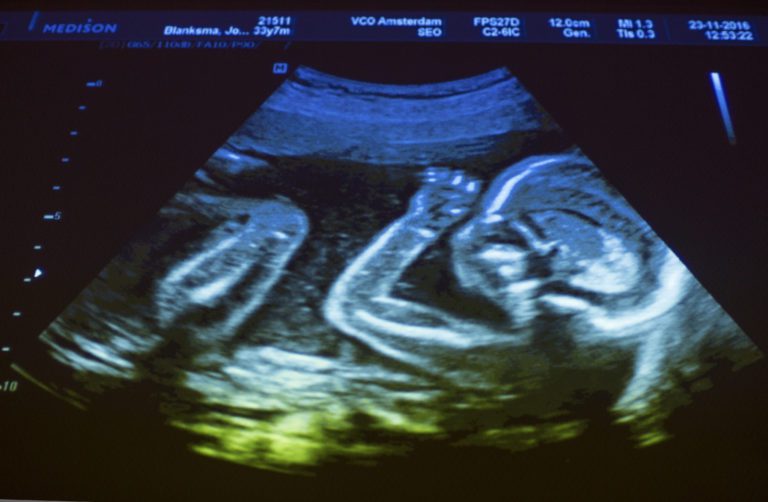

Statements from the University of Pittsburgh (Pitt) indicate one of its federally funded research projects utilized organs that might have been extracted from live fetuses, several scholars and doctors have said.

The issue emerged earlier this week when Judicial Watch (JW) released documents in which Pitt told the National Institutes of Health (NIH) it sought to “develop a pipeline to the acquisition, quality control and distribution of human genitourinary [urinary and genital organs and functions] samples obtained throughout development (6-42 weeks gestation).” According to NIH, 40 weeks is considered full term while after 42 weeks is considered “post-term” or “overdue.”